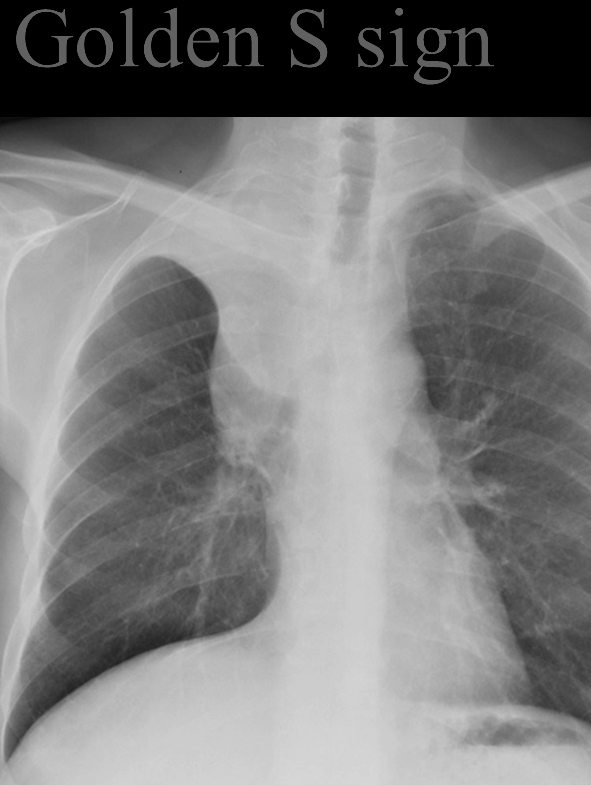

Golden S sign

RUL collapse and central mass